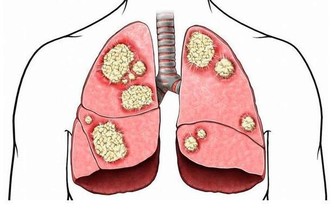

雖然痛在關節,病根卻出在軟骨上。軟骨是一種濃密的膠狀物質,它不僅強壯,而且比骨頭有彈性。

正常的膝關節有一層薄薄的軟骨,它們就像骨頭與骨頭間的「潤滑劑」,如果沒有它的保護,走路時就會骨頭磨骨頭,由於骨膜上的神經和血管豐富,因而會感到非常痛。

▲圖為關節軟骨。

令人遺憾的是,關節軟骨一旦受損,幾乎沒有再生能力,它沒有血管,主要靠周圍關節液提供養分。